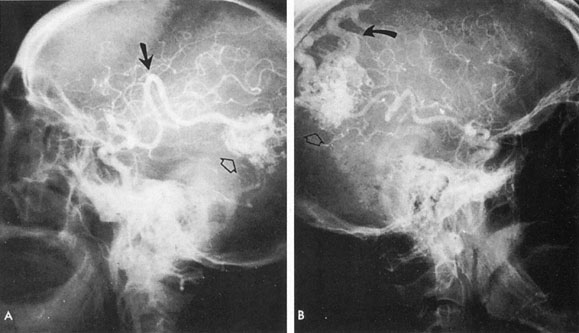

Tortuous or redundant basilar arteries are not uncommon in the older age group. Occasionally, gross dilation or ectasia develops so that the basilar artery acts as a mass in the posterior fossa. This phenomenon produces signs of low-pressure hydrocephalus, cranial nerve palsies, and long tract and sensory signs and may even simulate a cerebellopontine angle tumor or tumor at the foramen magnum.58 It is possible to diagnose such lesions with CT59 or MRI60 but angiography is definitive (Fig. 6). The association of insidious multiple cranial nerve palsies and long tract signs referable to a brainstem level, in an elderly patient with evidence of atherosclerosis, should make fusiform basilar artery dilation a diagnostic consideration.

Fig. 6. Fusiform basilar dilation. A: Lateral projection vertebral arteriogram showing a widened basilar artery (arrow) projecting beyond level of dorsum sellae. B: Anteroposterior projection showing a widened and tortuous basilar artery.

As opposed to saccular basilar aneurysms, fusiform aneurysms tend to occur in the older age group (older than 60 years) and are found predominately in men.2,36 They are commonly associated with hypertension and atherosclerotic cardiovascular disease, and a notable association with abdominal aortic aneurysms also exists.